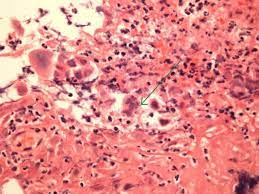

Pathology Of Herpes Simplex Virus Infection Dr Sampurna Roy Md from www.histopathology-india.net This condition occurs in the setting of patients with a weakened immune system who are susceptible. Esophagitis can occur from irritation from toxic or abrasive materials ingested or from gastric reflux. Infective esophagitis is a rare disease, affecting mostly immunocompromised patients. Very few cases of a multiple viral infection have been reported. Cobblestone esophagitis (эзофагит со слизистой булыжной мостовой). The latter can occur frequently during anesthesia or deep sedation. Healing and relapse of severe peptic esophagitis after treatment with omeprazole. Causes of esophagitis include stomach acids backing up into the esophagus, infection, oral medications and allergies.

Cytomegalovirus esophagitis is a form of esophagitis associated with cytomegalovirus. Herpes esophagitis is a viral infection of the esophagus caused by herpes simplex virus (hsv). Herpes esophagitis is a viral infection of the esophagus caused by herpes simplex virus (hsv). Symptoms include dysphagia, upper abdominal pain, diarrhea, nausea, vomiting, and sometimes hematemesis. Very few cases of a multiple viral infection have been reported. Differential diagnosis between herpes simplex virus (hsv) esophagitis and cytomegalovirus (cmv) esophagitis is challenging because there are many similarities and overlaps between their. Common forms of esophagitis include reflux esophagitis, infectious esophagitis, pill esophagitis candida esophagitis (see the image below) is the most common type of infectious esophagitis. Swallowed food and liquids normally pass through it. Eosinophilic esophagitis attributed to gastroesophageal re. Infective esophagitis is a rare disease, affecting mostly immunocompromised patients. Healing and relapse of severe peptic esophagitis after treatment with omeprazole. Esophagitis can occur from irritation from toxic or abrasive materials ingested or from gastric reflux. The esophagus is a tube composed of a mucosal lining, and longitudinal and circular smooth muscle fibers.

Pathology Of Herpes Simplex Virus Infection Dr Sampurna Roy Md from www.histopathology-india.net As the practice shows, hypodiagnostics of eosinophilic esophagitis and other eosinophilic gastrointestinal diseases takes place. Herpes esophagitis is a viral infection of the esophagus caused by herpes simplex virus (hsv). Herpes esophagitis is a viral infection of the esophagus caused by herpes simplex virus (hsv). Cytomegalovirus esophagitis is a form of esophagitis associated with cytomegalovirus. Peptic strictures cause a gradually progressive dysphagia for solid foods. Cobblestone esophagitis (эзофагит со слизистой булыжной мостовой). Healing and relapse of severe peptic esophagitis after treatment with omeprazole. We present a case of combined cytomegalovirus.

Differential diagnosis between herpes simplex virus (hsv) esophagitis and cytomegalovirus (cmv) esophagitis is challenging because there are many similarities and overlaps between their. Esophagitis can cause painful, difficult swallowing and chest pain. Healing and relapse of severe peptic esophagitis after treatment with omeprazole. Esophagitis can occur from irritation from toxic or abrasive materials ingested or from gastric reflux. Causes of esophagitis include stomach acids backing up into the esophagus, infection, oral medications and allergies. The latter can occur frequently during anesthesia or deep sedation. Very few cases of a multiple viral infection have been reported. Herpes esophagitis is a viral infection of the esophagus caused by herpes simplex virus (hsv). Esophagitis may cause odynophagia and even esophageal hemorrhage, which is usually occult but can be massive. We present a case of combined cytomegalovirus. Eosinophilic esophagitis attributed to gastroesophageal re. Swallowed food and liquids normally pass through it. Esophagitis, also spelled oesophagitis, is a disease characterized by inflammation of the esophagus.

February 3 2020 Week 2 School Of Medicine Pathology Uab from www.uab.edu This condition occurs in the setting of patients with a weakened immune system who are susceptible. Symptoms include dysphagia, upper abdominal pain, diarrhea, nausea, vomiting, and sometimes hematemesis. Occurs with patients who have oral lesions reflux esophagitis 1. Esophagitis can cause painful, difficult swallowing and chest pain. Infective esophagitis is a rare disease, affecting mostly immunocompromised patients. Esophagitis may cause odynophagia and even esophageal hemorrhage, which is usually occult but can be massive. The esophagus is a tube composed of a mucosal lining, and longitudinal and circular smooth muscle fibers. Very few cases of a multiple viral infection have been reported.